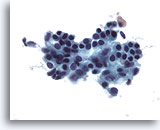

Figure 28: Breast FNA, Ductal carcinoma in situ. This is a cellular aspirate showing clusters of tumor cells, single malignant cells and foamy macrophages. Ductal carcinoma in situ (DCIS) often shows myoepithelial cells overlying the malignant cell clusters. Tumor cells tend to be clustered rather than single as in invasive tumor. In addition, tubular structures are not associated with DCIS. Comedo DCIS is characteristically associated with necrosis and calcium. 40x

Figure 28

Breast FNA, Ductal carcinoma in situ.

This is a cellular aspirate showing clusters of tumor cells, single malignant cells and foamy macrophages. Ductal carcinoma in situ (DCIS) often shows myoepithelial cells overlying the malignant cell clusters. Tumor cells tend to be clustered rather than single as in invasive tumor. In addition, tubular structures are not associated with DCIS. Comedo DCIS is characteristically associated with necrosis and calcium.

40x